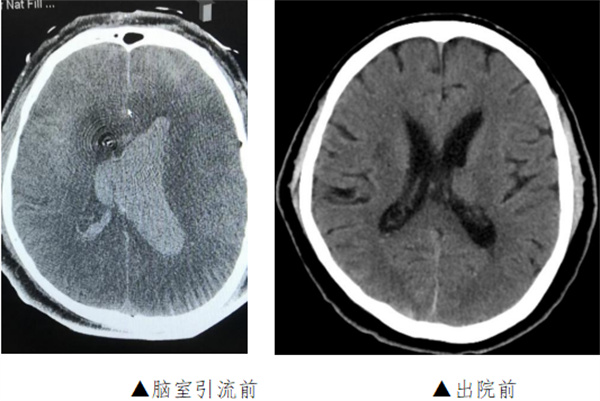

手术于复合手术室进行。先用血管造影机行CT检查提示脑室出血增多,脑室铸型,急性脑积水形成。团队立即行左侧脑室钻孔引流术,于左侧脑室内放置脑室引流管,颅内压极高,引流血性脑脊液。随后行脑血管造影提示左侧大脑前动脉A2段动脉瘤,团队采取微创治疗,应用支架辅助,于动脉瘤内填入3枚弹簧圈,造影显示动脉瘤完全闭塞,载瘤动脉通畅。手术历时3小时,手术完毕后行CT检查未见新发颅内出血,脑室引流管位置良好。

术后患者转入ICU,接受机械通气、镇静镇痛、防治脑血管痉挛、脱水降颅压等治疗。复查头颅CT见颅内出血逐渐减少,无脑梗死及脑积水。术后一周拔除脑室引流管,行气管切开术。患者病情逐渐好转,术后3周脱离呼吸机,转至当地康复医院继续治疗。出院时患者能自动睁眼,左侧肢体可活动。